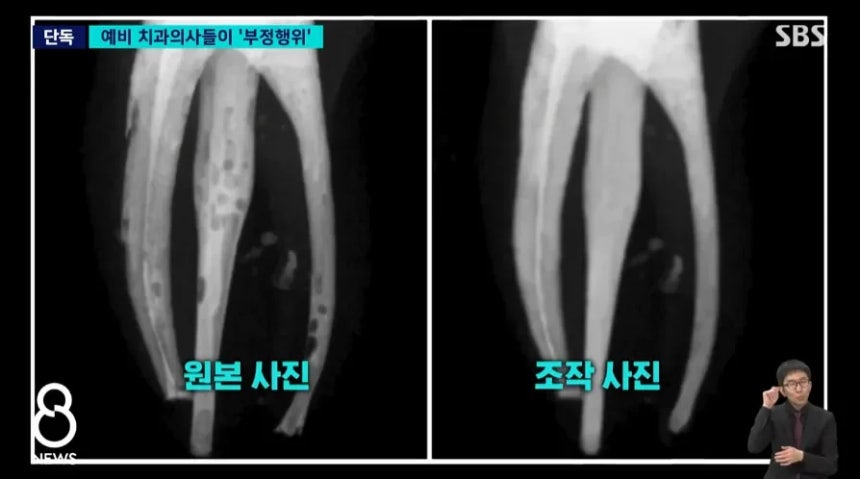

[여시뉴스데스크]‘포토샵으로 깨끗하게~’ 연세대 치대생들 실습 사진 무더기 조작, 징계 받아

[헤럴드경제=한지숙 기자] 연세대 치과대학 학생들이 최근 무더기로 부정행위를 저질러 징계를 받은 사실이 드러났다.

이 실습 과정에는 의사면허 국가시험을 앞둔 본과 4학년 59명이 수강했는데, 이 중 34명이 이처럼 과제물 결과를 포토샵으로 조작하거나 서로의 결과물을 베껴서 낸 것으로 파악됐다.